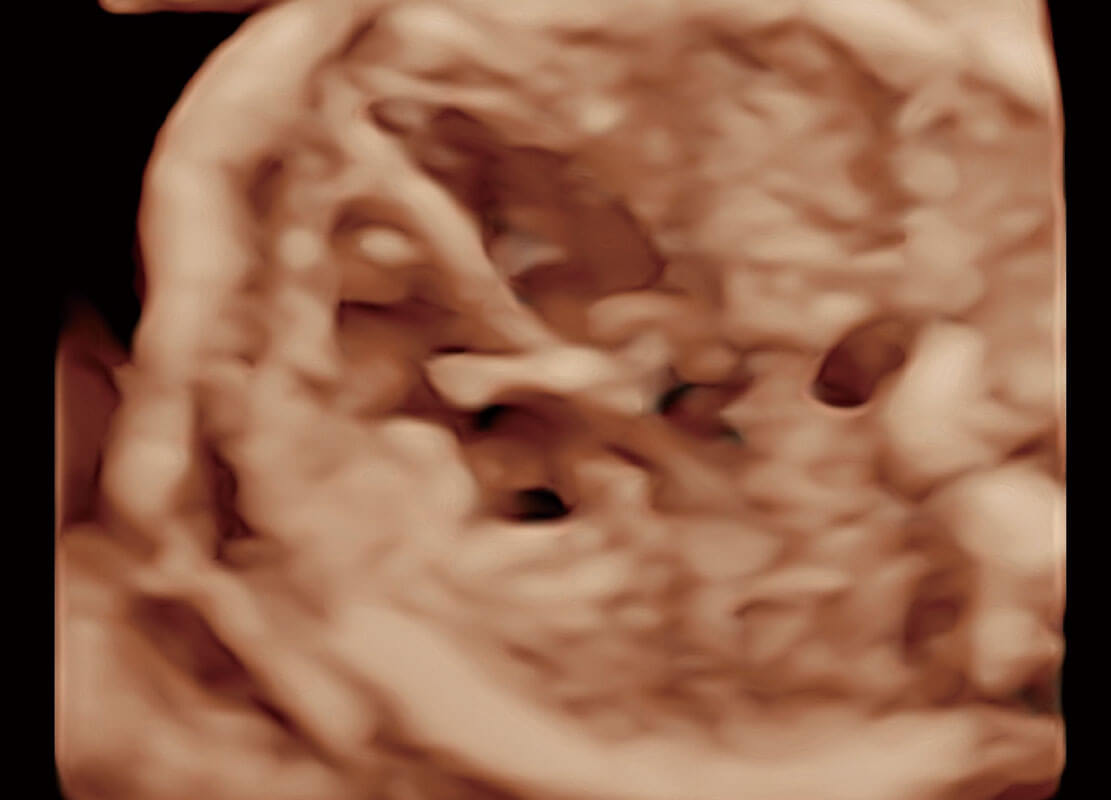

P60在胎儿早孕期超声筛查中为您带来优异的图像质量。

早孕-胎心

高分辨率容积成像-早孕胎儿

胎儿体循环